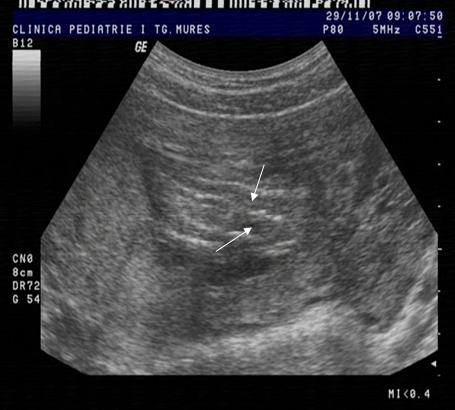

Fig nr.119 Coloana fetala la un defect fetal larg de tub neural , diagnosticat la 12 saptamani gestationale.Se remarca lipsa paralelismului celor doua linii de osificare, ca si deformarea coloanei ( cu sageti )

Fig .nr.120 Sectiune transversala la rahischiza descrisa in figura precedenta.Cu sageata e marcata lipsa inchiderii vertebrale